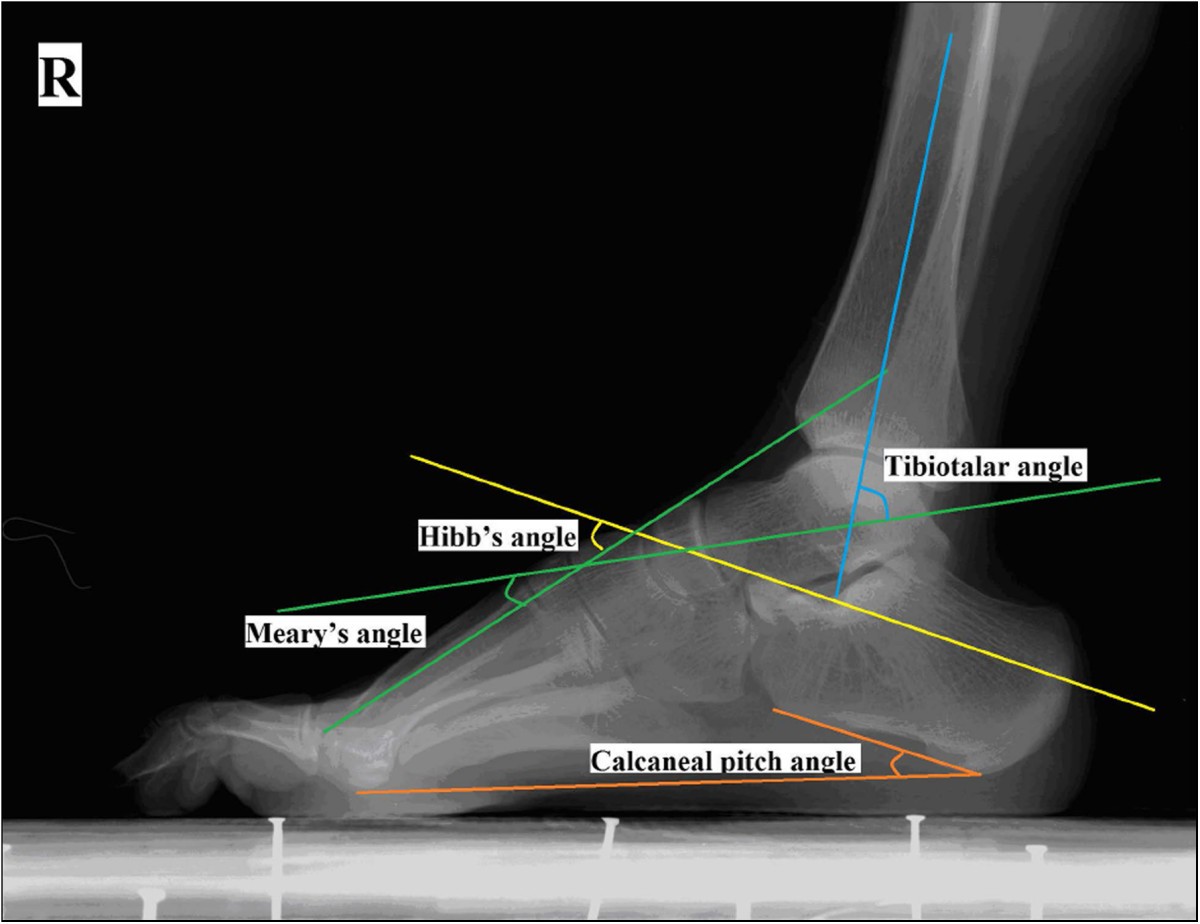

A weightbearing lateral radiograph of a normal foot of a 53 year old Calcaneal Pitch Angle Measurement Mean calcaneal pitch angle and meary's angle: The calcaneal inclination angle, also known as the calcaneal pitch, is useful in assessing medial arch height. If < 20 degrees then pes planus. Angle formed by the horizontal and a line from the base of heel & inferior cortex of calcaneus (figure 1). Compare to pes planus (figure 2). The radiographic angles. Calcaneal Pitch Angle Measurement.